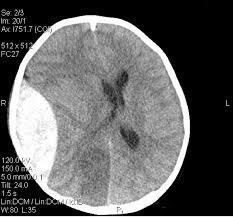

Question 3

Question

La hemorragia extradural:

Image:

3a9e4833-f5f5-4a03-8065-67acfa2c2c94 (image/jpg)

Answer

A- Se produce entre la duramadre y la superficie externa de la aracnoides-

B- No se suele asociar a una fractura del cráneo-

C- Se debe a un sangrado por las venas corticales.

D- Puede asociarse a un período lúcido tras el traumatismo.

E- Necesita una cirugía urgente-